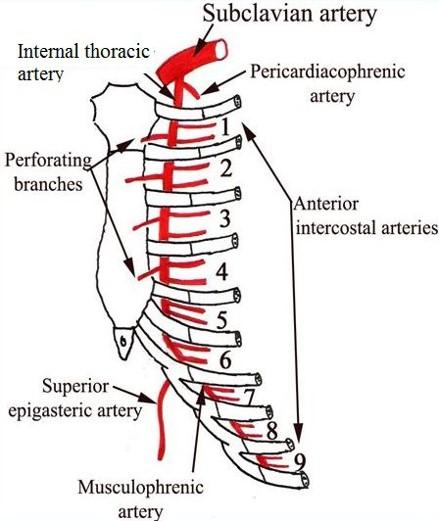

- Blood supply to the rib cage originates from what 2 places?

- what 2 arteries supply the intercostal spaces of the rib cage

- what branch off of the subclavian artery goes down specifically to the diaphragm?

aorta and subclavian artery

Anterior and posterior intercostal arteries

notice how branches from the aorta go around and supply the rib cage

the internal thoracic artery

look at picture

study picture

go back and rememeber the subclavian artery and how it had the VA, the thyrocervical trun and the costocervical trunk.....one branch from the costcervical trunk that went up to the skull was the deep cervical artery....what is the branch of this trunk that goes down?

what then branches from the artery?

the supreme intercostal artery

the 1st and 2nd posterior intercostal arteries

notice the subclavian, the costcervical trunk and the deep cervical artery and the supreme intercostal artery...then notice how it splits off into 2 branches under the clavicle

the 3rd through the 11th intercostal arteries branch off from what?

notice it in the picture?

from the aorta

Anterior intercostal arteries:

- These arteries branch from where?

- then this originates from where?

internal thoracic artery

- Internal thoracic artery originates from subclavian artery

the internal thoracic artery comes from the ____________ vein and then runs behind the anterior ________?

subclavian vein

anterior sternum

notice the internal thoracic artery coming down right near the sternum

The Anterior intercostal arteries supply which intercostal spaces?

- The lower intercostal spaces supplied by what?

1-9

posterior intercostal arteries

notice how the intercostal arteries run superior and inferior in the intercostal spaces